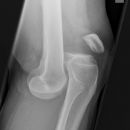

Traumatische Epiphysenlösung

Es wurden keine Bilder gefunden.